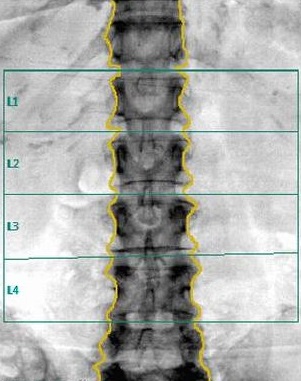

L’os absorbe les photons qui le traversent en partie. Un détecteur de photons est installé de l’autre côté de l’os. Plus l’os est dense, moins nombreux sont les photons qui atteignent le détecteur. La mesure du rayonnement après la traversée de l'os donne donc un renseignement sur sa densité. Pour obtenir une indication de l’ensemble du squelette, il suffit de mesurer deux sites seulement: l’os de la colonne et celui de la hanche. Parfois on mesure le poignet, ou même, exceptionnellement, le corps en entier.